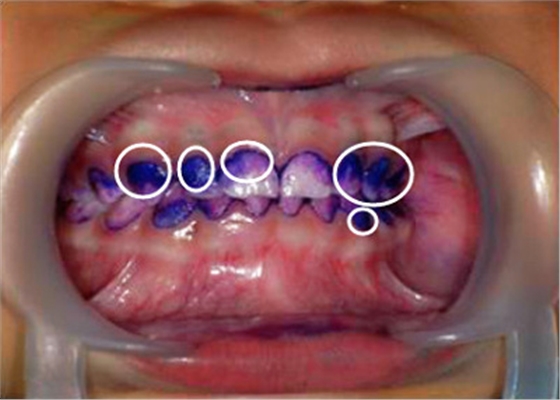

▲顏色較深的區(qū)域,就是牙菌斑堆積數(shù)較多的地方▼

如果牙齒刷得足夠干凈

牙菌斑指示劑就沒法染色到牙齒上

相反,顏色越深的地方

就說明堆積的牙菌斑越多

② 牙菌斑染色,讓你更直觀了解口腔內(nèi)菌斑情況。

【圖中:紫色染色處為涂抹在牙齒上的菌斑顯示劑】

【圖中:顧客可直觀了解到自己口腔內(nèi)牙菌斑情況】

天天刷牙難道還會長很多牙菌斑?別不信,讓菌斑染色劑染色一下就知道了。直觀的提醒你,哪顆牙齒被你刷牙時疏忽了。